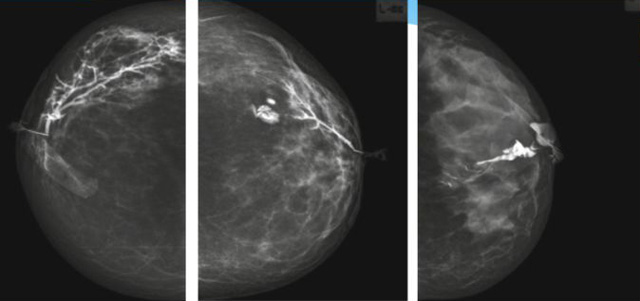

乳腺导管内乳头状瘤分为以下两个,位于乳晕区大导管的中央型乳头状瘤,起源于末梢导管小叶单位的外周型乳头状瘤。外周型乳头状瘤常常没有明显的的临床表现,常因X线或乳腺成人抖音视频APPP在线观看检查发现。重点要关注的是中央型乳头状瘤,发生于任何年龄的女性,以40~50岁者居多。它表现为:单侧乳头溢液,特别是血性溢液少数病人可在乳晕区触及肿块。从病理学上面讲表现为导管上皮和间质增生形成有纤维脉管束的乳头状结构。这是它一个病理学上的表现。它的超声表现为:病变导管囊状扩张呈无回声,内可见乳头状低回声或中等回声。乳晕处的导管扩张,管腔内可见边界清楚的,低回声实性结节。外周型导管内乳头状瘤可,表现扩张为为低回声的实性结节,CDFI:部分肿瘤可显示为轴心性的看到血流信号。乳腺增生症:可见导管扩张,内无乳头状实性回声,导管内乳头状癌:囊内乳头状癌病变较大,不规则,厚基底,血流丰富。以囊性为主的混合回声,形态不规则,内见实性低回声实性低回声可见少量血流,病理为囊内乳头状癌。

乳腺成人抖音视频APPP在线观看检查的价值在哪里呢?它可以检查发现乳晕周围的各种病变,对于单侧乳头溢液、血性溢液的患者,超声是首选的影像学检查方法。注意:导管内乳头状瘤可合并不典型增生或,导管内乳头状癌,手术前怀疑时候,就应该手术切除而不是用微创手术。